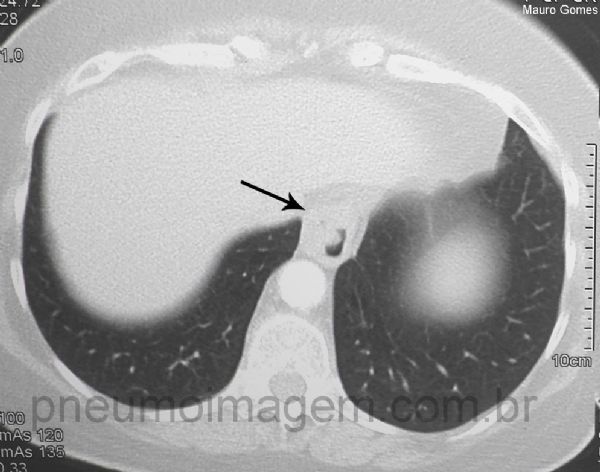

Corte demonstrando a hérnia hiatal (seta preta) indicando que a provável causa da PAC foi a doença do refluxo gastresofágico (DRGE). Chaves: hérnia de hiato; hérnia do hiato.

Hiatal hernia (black arrow) indicating that the probable cause of the CAP was to gastroesophageal reflux disease (GERD). Keys: hiatus hernia.